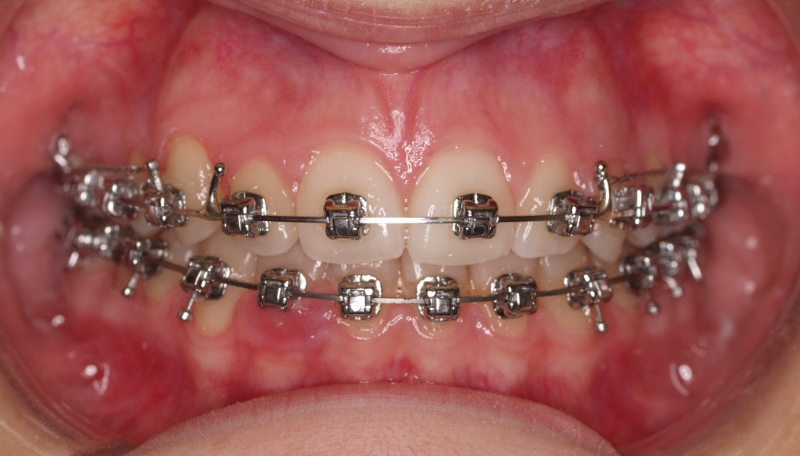

La paciente O.O. acude a nuestra consulta por:

– Canino 13 e incisivo lateral 42 en posición ectópica.

– Canino 23 incluido.

Con lo que decide realizarse un tratamiento de ortodoncia de duración de 24 meses con brackets damon Q.